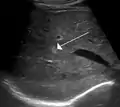

ورم وعائي دموي في الكبد كما يظهر في صورة الأمواج فوق الصوتية.